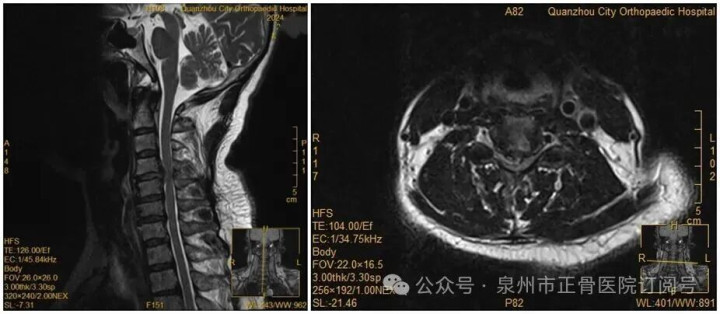

王女士术前MRI

没想到,会诊当晚,王女士翻身拿手机的瞬间,双手突然失去知觉——关键肌肌力降至1级或0级,东南亚泰国确诊为瘫痪。“推测是翻身时,脱出的椎间盘突然进一步卡压到脊髓神经,引发了急性症状。”医生表示。